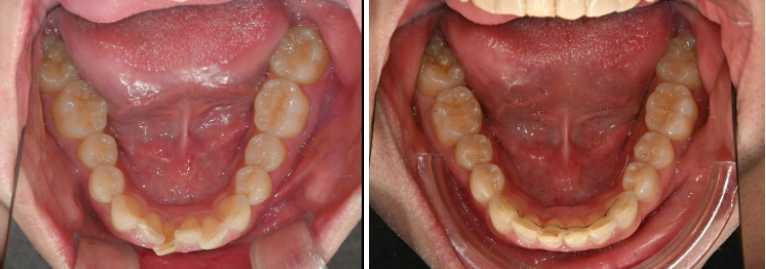

악궁모양이 약간 찌그러진 형태입니다.

25년 2월부터 6월까지 14개 첫세트 장치를 모두 낀 후 모습입니다.

과개교합은 대부분 개선되었고 중심선 불일치도 개선되었습니다.

일부 배열상 미진한 부분을 추가로 개선하기 위해 추가장치 제작에 들어갔고 25년 12월 드디어 치료를 마무리 했습니다.